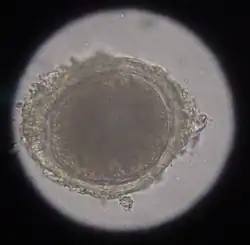

The approximately 85 μm egg of toxocara mystax in the microscopic image.

The most common roundworm in most cats is toxocara mystax (syn. toxocara cati), infestation with toxascaris leonina is less common. Only in ocelots in Texas was T. leonina detectable in every animal, making it the most common parasite,[2] and in bobcats in Nebraska it was observed almost as often as T. mystax.[3] Both species of roundworm occur worldwide and roundworm infestation is a very common endoparasitosis. The adult roundworms, up to 10 cm long, live in the small intestine. The female worms produce a large number of eggs, which are released into the environment with the feces. The infective larvae develop in the eggs after about four weeks.

In the case of worms in vomit, the diagnosis can already be made without special examinations. A roundworm infestation can be detected with relative certainty by microscopic detection of the eggs extracted from the feces using the flotation method.